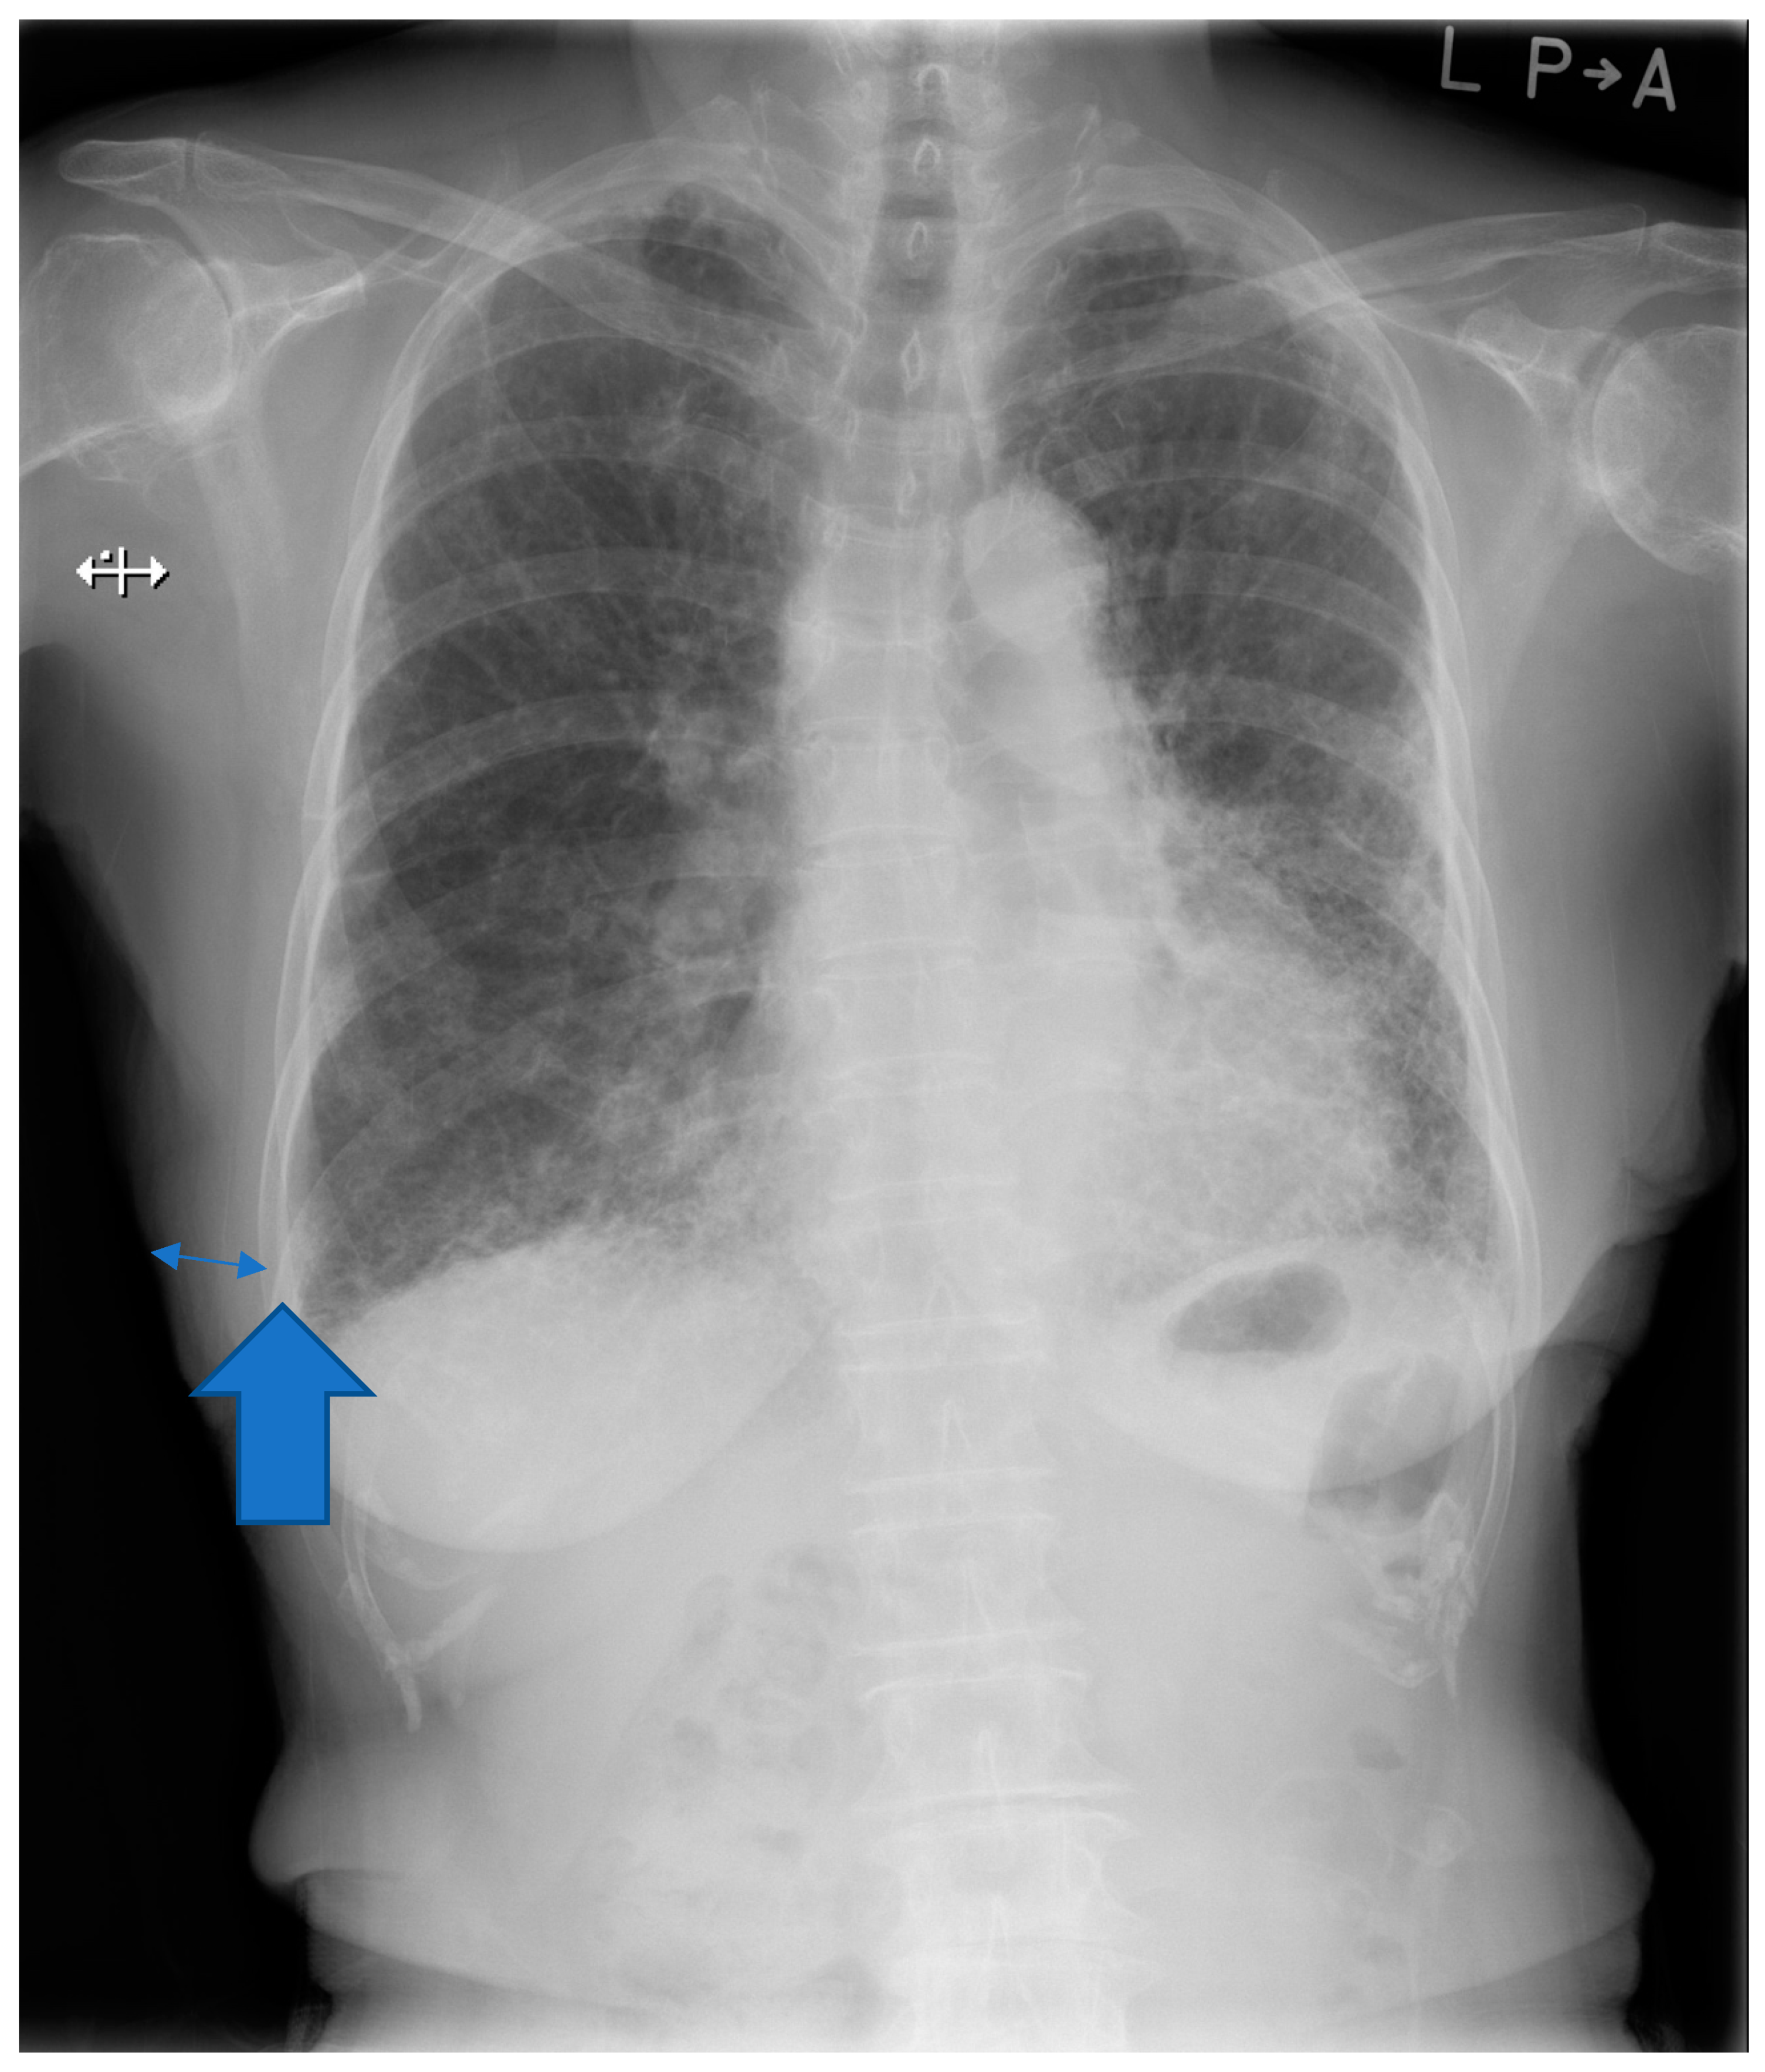

| Soft tissue thickness (mm) | 26.4 ± 8.8 (1.7–52.2) |